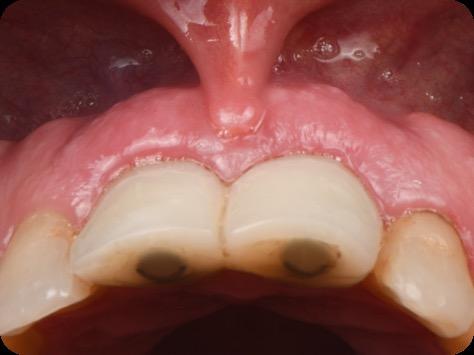

Black triangles and diastemas can cause entrapment of the food and accumulation of bacteria, which leads to gingivitis and ultimately periodontitis. By eliminating the black triangles and diastemas with composite bonding, the dentist not only improves the aesthetics, but also protects the long-term health of the periodontal tissues.

Restoring incisal wear and closing diastema with G-aenial A’CHORD. Courtesy of: Dr Aleksandra Slacan, Poland

Reshaping of teeth and diastema closure with G-aenial A’CHORD. Courtesy of: Dr Andres Silva, Spain